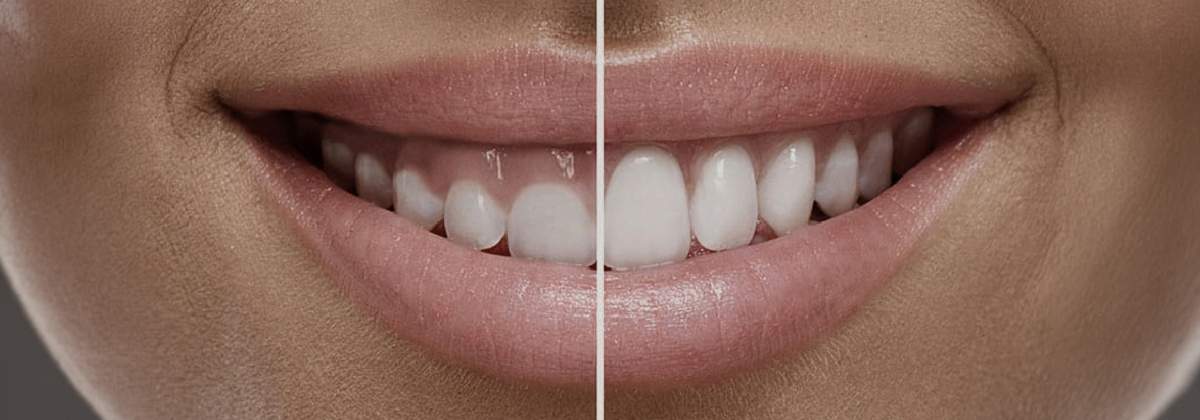

😁Correção do Sorriso

Gengival (Gummy Smile)

Gengival (Gummy Smile)

Gengivectomia estética e alongamento coronário com remodelação óssea. Resultado definitivo e transformador — o sorriso que você sempre quis.

Estética gengivalVeja o que dá pra melhorar →

Quando aparece muita gengiva ao sorrir, os dentes parecem mais curtos do que realmente são. É o chamado sorriso gengival. Fazemos a correção no consultório. Veja o caso clínico e se informe mais logo abaixo:

O que é

O que fazer

Planejamento digital do sorriso

Em casos mais complexos, o Dr. Luís planeja a correção no computador, sobre fotos do seu sorriso — medindo cada milímetro antes da cirurgia. Assim, o resultado é previsível e fica da melhor forma possível.